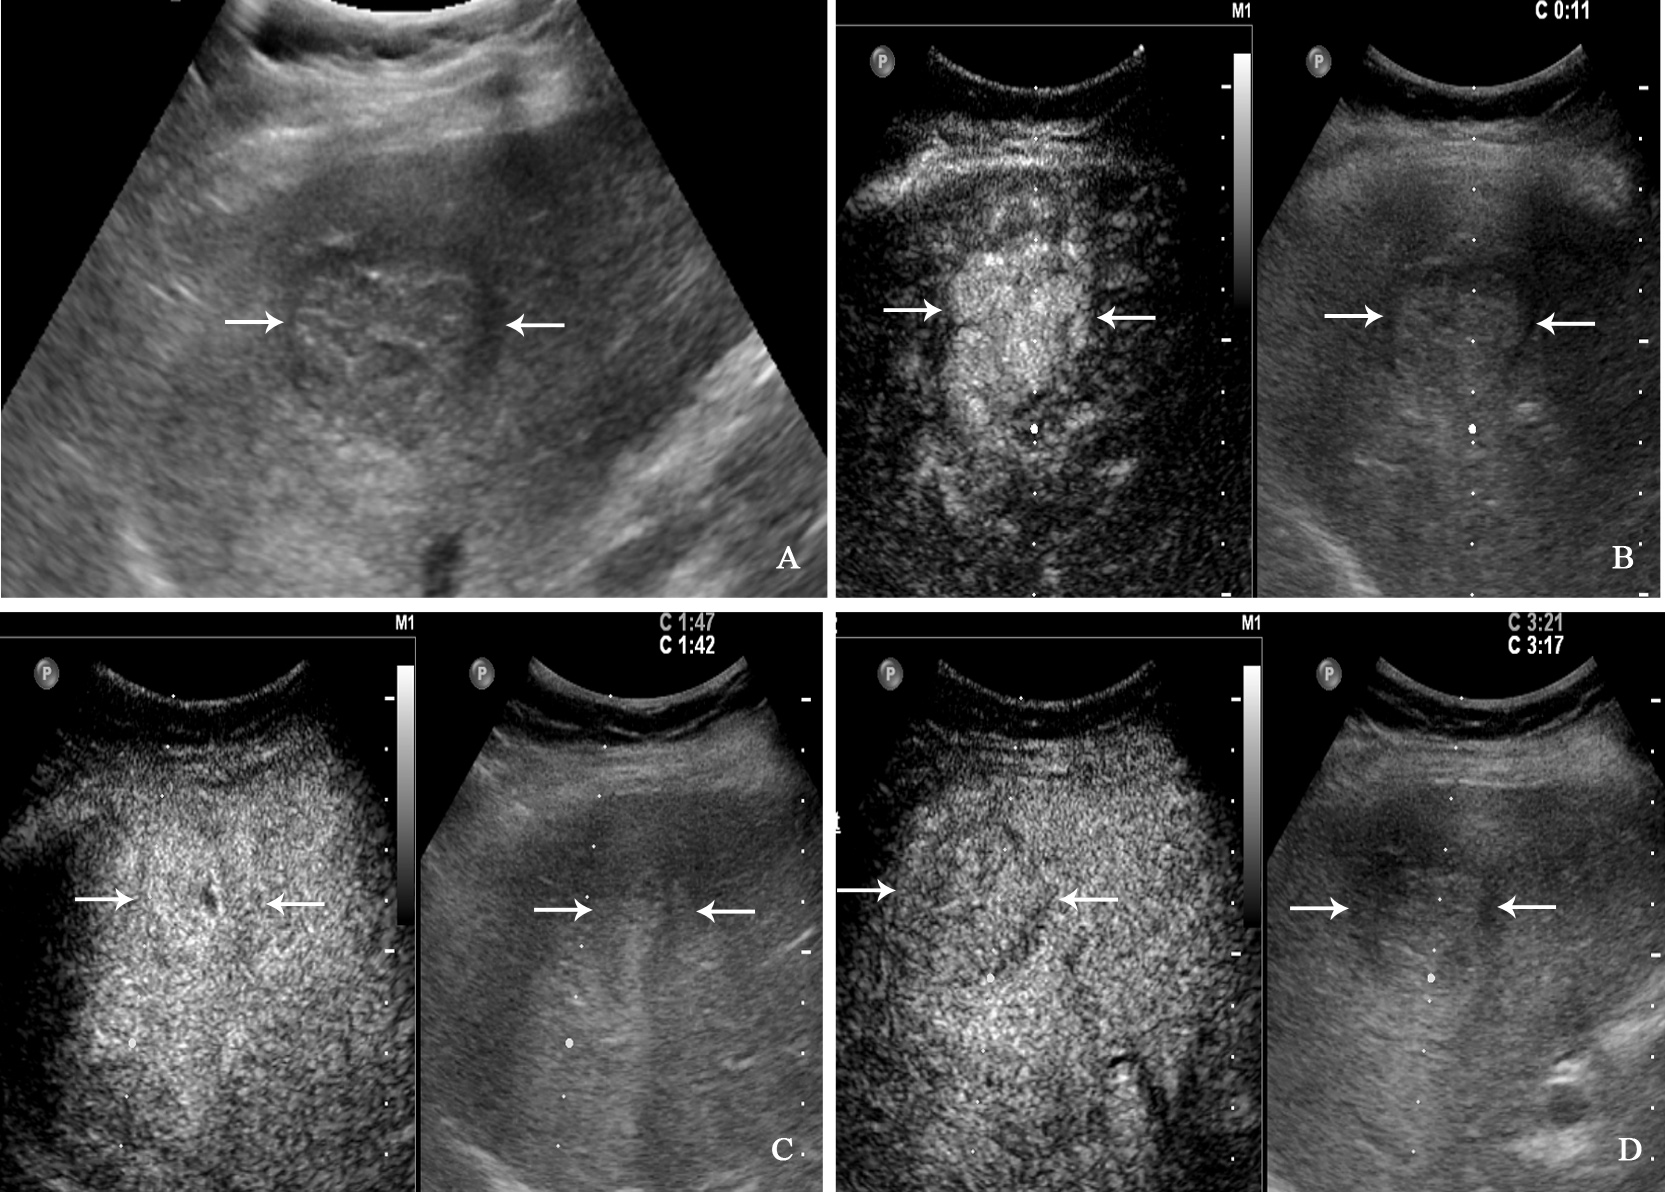

Figure 4

A 71-year-old man with hepatocellular carcinoma. The patient had no chronic hepatitis B and C Conventional ultrasound showed that a hypoechoic tumor with largest diameter of 3.8 centimeters in right liver lobe (A). In the arterial phase of contrast-enhanced ultrasound, the tumor showed homogeneous hyperenhancement (B), and isoenhancement in the portal venous phase (C), finally with slightly washout in the late phase (D).